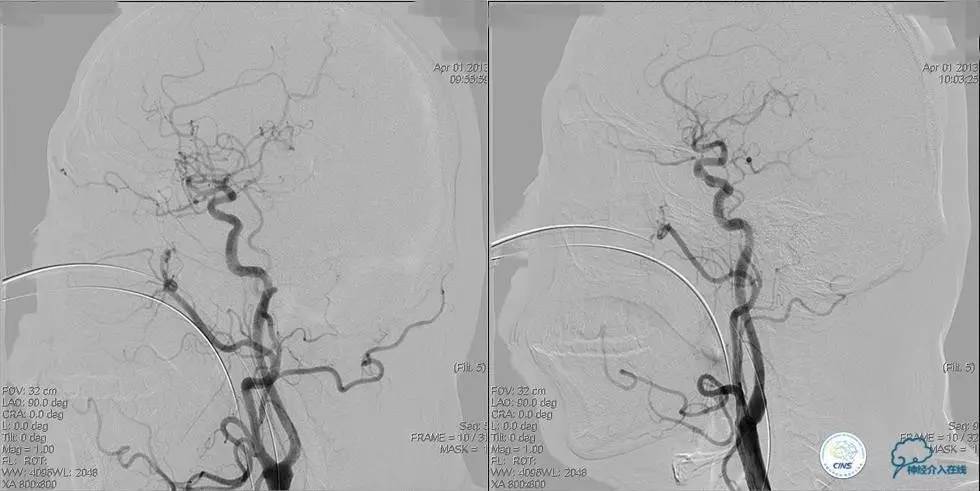

▼术前DSA

▼术中DSA

▼术后DSA